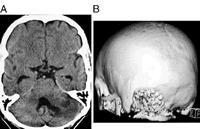

据研究者介绍,2000年1月至2004年9月间,他们一共对10例颅后窝病变行颅骨切除术的患者,在同一手术室进行了上面介绍的颅骨重建术。患者没有出现并发症和延迟的重建部位疼痛。术后颅骨的平面X线和CT结果显示外科缺损处良好的愈合和成形情况。, 百拇医药